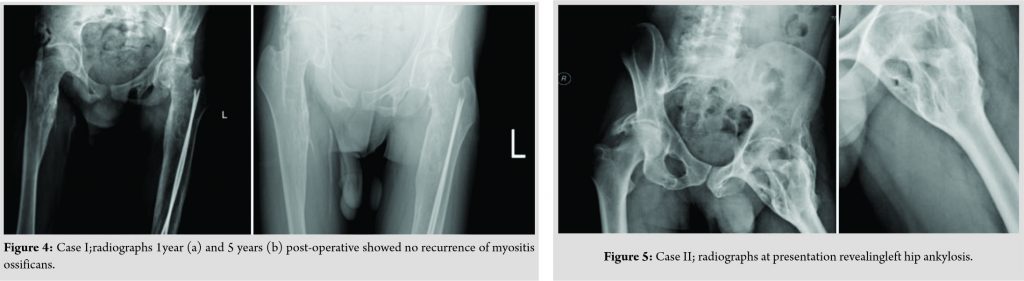

Radiographs of the hip joints revealed evident ossification that suggested the diagnosis of MO (Fig. 1). Moreover, 3-dimentional (3D)-CT scan(Fig. 2)revealed anterior and posterior ossification around the hip joint bilaterally. Importantly, however, the HO was separated from the actual femur bone and hip joint by soft tissue. Serum alkaline phosphatase (SAP) level was within normal limits and bone scan was normal. The patient underwent successful staged excision of the ossifications; the right side followed by the leftside after 1 month (Fig. 3). Upon recovery from the operation, the patient was able to walk independently with residual hip flexion. Postoperatively, he received physiotherapy and indomethacin (75 mg PO for 6 weeks) to prevent a recurrence. Follow-ups over 5 years demonstrated achievement of community ambulation without assistance and no signs of recurrence of MO (Fig. 4).

Upon recovery from the operation, the patient was able to walk independently with residual hip flexion. Postoperatively, the patient received physiotherapy and indomethacin (75 mg PO for 6 weeks) to prevent a recurrence. Follow-ups over 4 years demonstrated the full function of the affected limb and no signs of recurrence (Fig. 8).